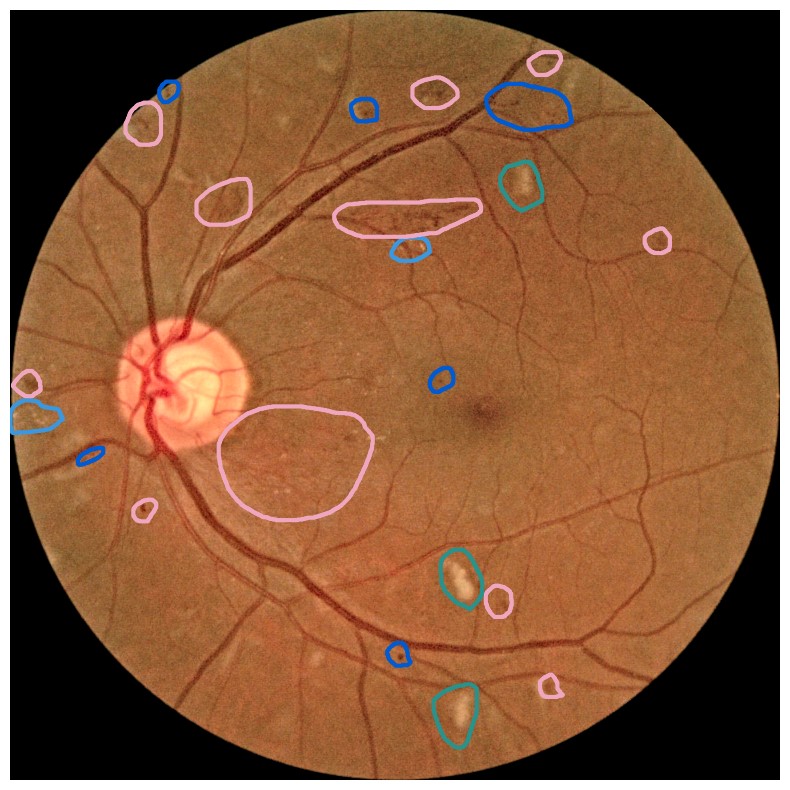

Diabetes is a disease with increasing prevalence, and diabetic retinopathy (DR) is one of the most common complications (World Health Organization, 2022). \AcDR is characterized by retinal abnormalities, which damage the eye and can lead to blindness. Its severity depends on the type and amount of retinal abnormalities: \AcHE, microaneurysms (MA), hard exudates (EX), soft exudates (SE), intraretinal microvascular abnormalities (IRMA), and neovascularization (NV). \AcDR is graded from 00 to 4444 (no DR, mild, moderate, and severe nonproliferative DR, and proliferative DR), as described by Wilkinson et al. (2003). DR grading of fundus images is traditionally a manual process requiring medical expertise. Figure 1 provides examples of fundus images of eyes with increasing severity of DR including the ground truth segmentations of the six retinal abnormalities. These images underline the challenge of identifying relevant medical abnormalities without specialist training.

Figure 1: Example fundus images representing increasing DR severity with segmentation masks of retinal lesions. Level 4 is the most severe type of DR and is associated with a high risk of blindness. Images from the FGADR dataset (Zhou et al., 2021). Dark blue = microaneurysms, pink = hemorrhages, light blue = hard exudates, green = soft exudates, yellow = intra-retinal microvascular abnormalities, and red = neovascularization. Best viewed with zoom.

Concept explanation methods are attractive for medical applications because they measure how much the deep neural networks are influenced by high-level concepts representing clinical findings (Salahuddin et al., 2022). A concept can be described as a theme or topic, e.g., ’stripes’ and ’dots’ for natural images, or diagnostic findings such as ’hemorrhages’ and ’microaneurysms’ for fundus images. The six different diagnostic concepts used for this work is shown with the ground truth segmentation masks in Figure 1. \AcTCAV (Kim et al., 2018) and Concept Bottleneck Models (Koh et al., 2020) are two concept-based methods that have several advantages above heatmap methods. Both allow the user to define the concepts, which ensures relevant and meaningful concepts that are interpretable for the end-users. How the concepts are used varies between the two explanation methods and is outlined in Sections 2.1 and 2.2. Moreover, the relative importance of the concepts can be quantitatively measured. For Testing with Concept Activation Vectors (TCAV), concept scores can be generated for a group of images, e.g. images belonging to the same class, allowing the user to investigate whether the model has learnt aspects coherent to domain knowledge and diagnostic guidelines. CBMs, on the other hand, allow the user to directly modify the model’s intermediate concept predictions at test time and observe how this affects the final model prediction. This way of manipulating the model after training is attractive in the medical field, e.g. if the clinician wants to increase the emphasis of a concept in the image that the model missed. While TCAV explains models post-hoc, i.e., predicting the concepts after the classification model has been trained, CBMs provide ad-hoc explanations, where the prediction of the concepts are trained together with the classification model. Even though concept explanations can be more intuitive than heatmaps for medical doctors, neither TCAV or CBMs have been extensively studied in the field of DR grading. In this work, we thus investigate and compare TCAV and CBMs for explaining deep neural networks trained to grade DR in fundus images.